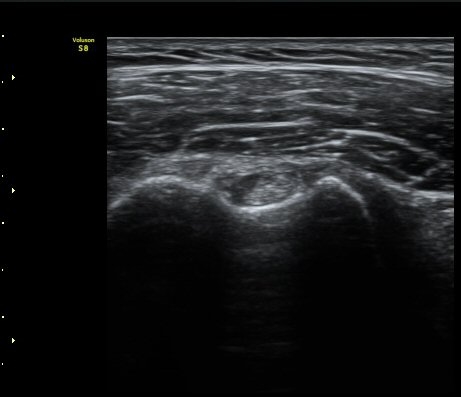

¼ºº° / ³ªÀÌ

¿©ÀÚ/ 50¼¼

ÁÖÁõ»ó

³Ñ¾îÁø ÈÄ ½ÉÇØÁö´Â ¾î±úÀÇ ÅëÁõ°ú °­Á÷

º´·Â

³Ñ¾îÁø ÈÄ ¾î±úÀÇ ÅëÁõÀÌ ¹ß»ýÇÏ¿© Ÿ º´¿ø ³»¿øÇÏ¿© ¿¢½º·¹ÀÌ °Ë»ç¿¡¼­ ƯÀÌ ¼Ò°ß ¾ø´Ù´Â ¼Ò°ßÀ» µè°í Áö³ÁÀ¸³ª ¾î±úÀÇ ÅëÁõÀÌ ½ÉÇØÁö°í Á¡Á¡ ¾î±ú°¡ ±»¾îÁ® ³»¿ø

ÃÊÀ½ÆÄ °Ë»ç